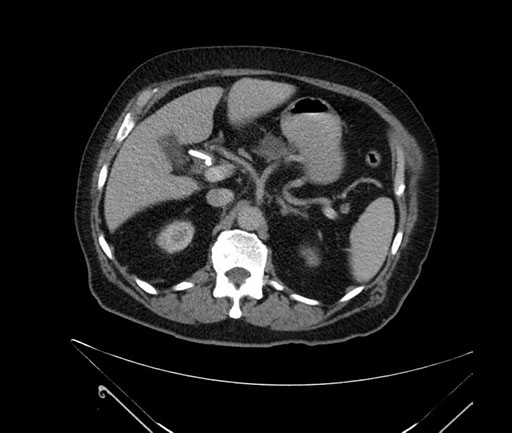

Whipple (pancreaticoduodenectomy) [case 7]

Imaging Analysis

Look through the patient's CT scan to identify any areas of concern for the necessary procedure.

Based on your CT findings, which issue(s) would give reason for "planned slowing down moment(s)" in this case?

Considering a standard Whipple procedure, what step(s) of the operation would you do differently in this case?